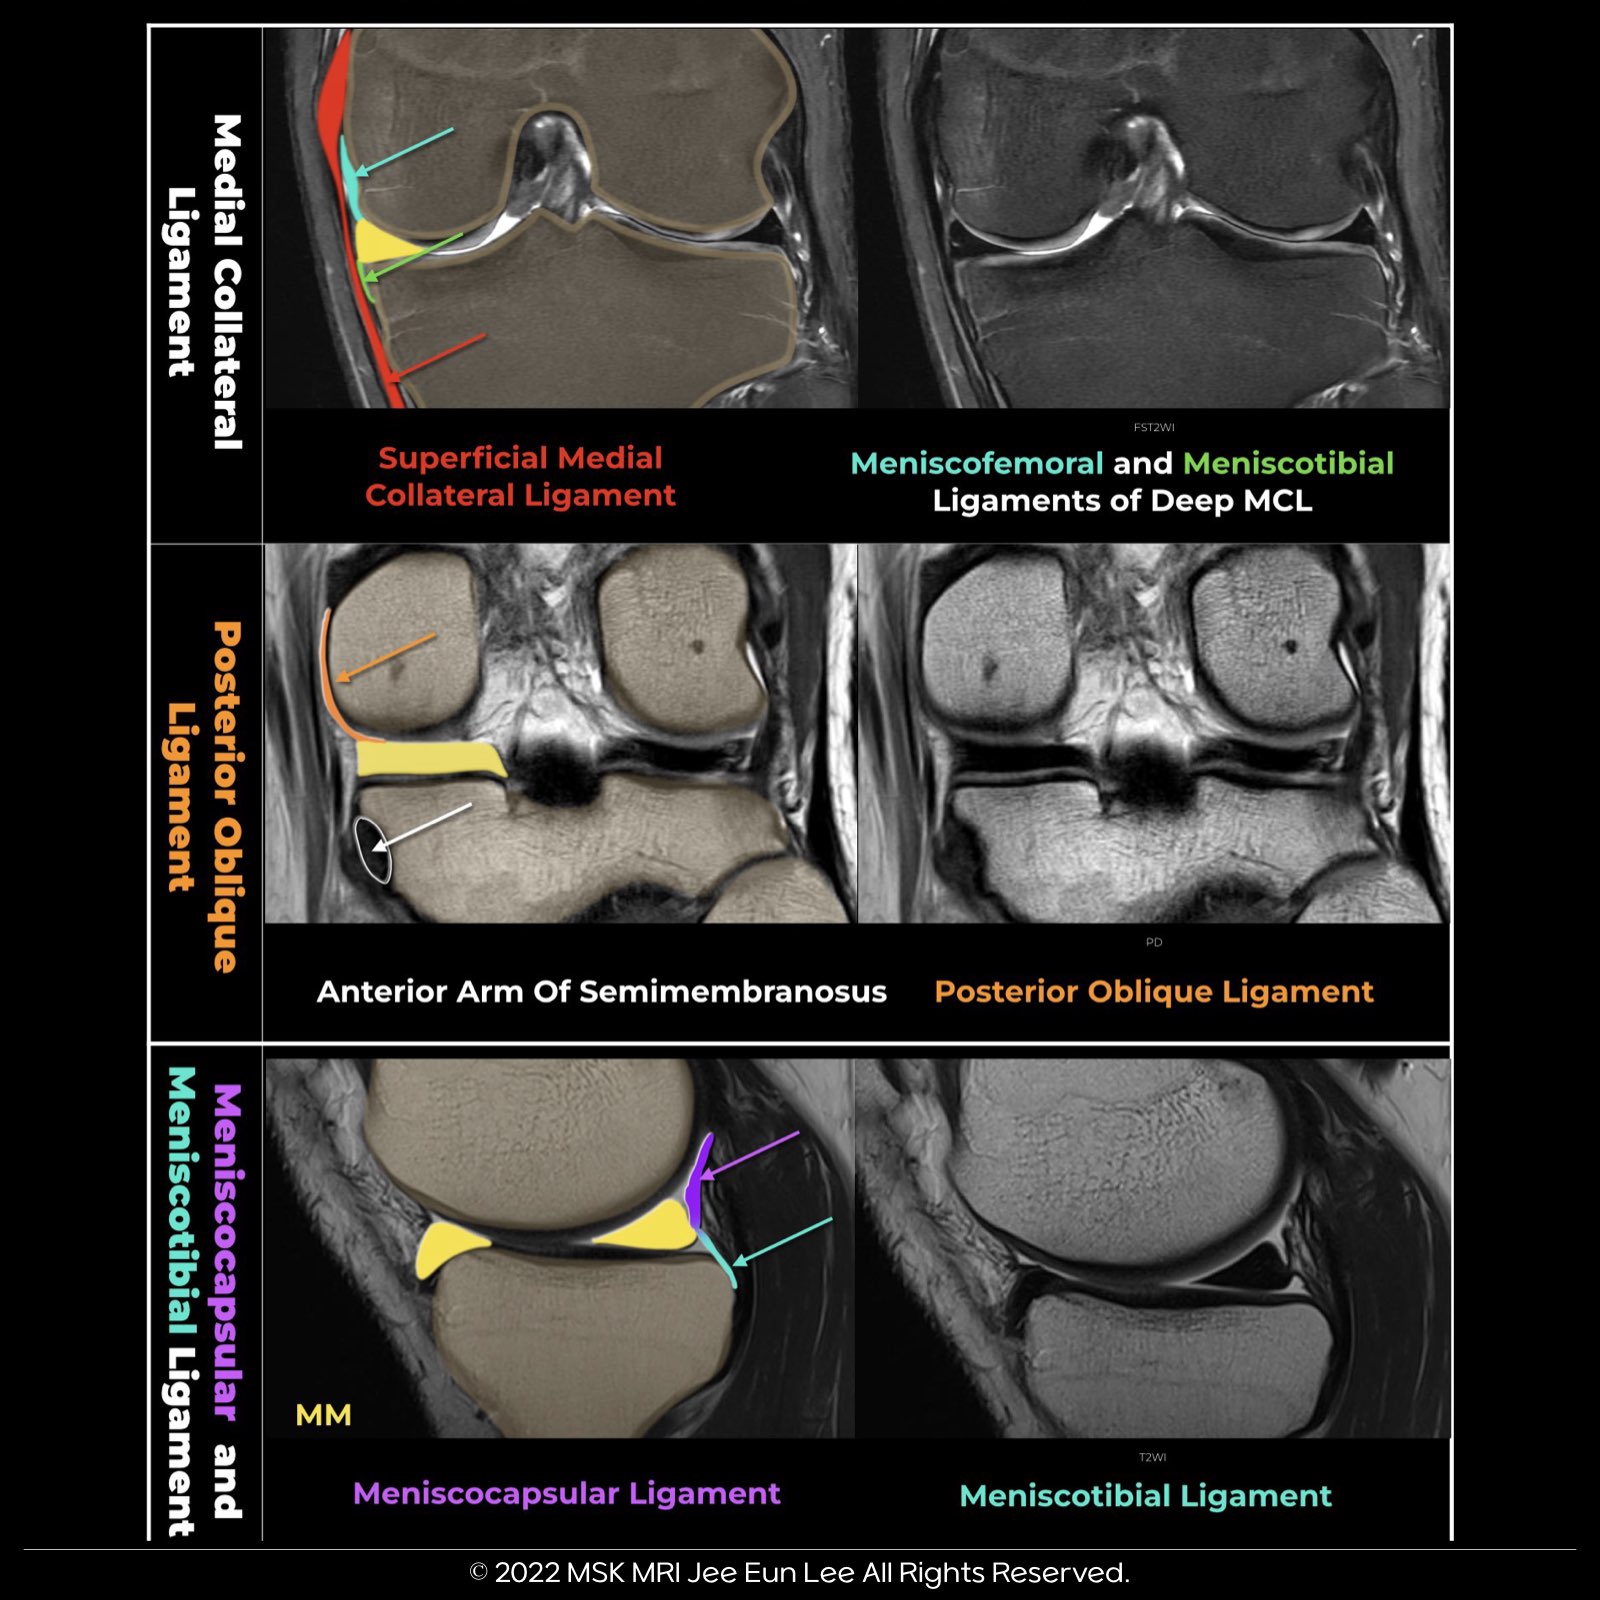

The knee joint capsule, part of layer III, forms the deep MCL, with its meniscotibial and meniscofemoral components, along the medial aspect of the knee. It then continues posteriorly, where it is reinforced externally by the POL and expansions from the semimembranosus.

More posteriorly, the posteromedial joint capsule passes deep to the medial head of the gastrocnemius. The two peripheral attachments of the MM’s posterior horn are the meniscocapsular ligament, extending posterosuperiorly to the capsule, and the meniscotibial ligament, which attaches inferiorly to the tibia.

The dMCL connects the meniscus to the femur and the tibia in the medial part of the knee and is a thickening of the medial joint capsule (layer 3)

It extends distally from posterior to anterior and terminates in a fan-like wide attachment on the tibia. The dMCL had firm meniscofemoral and meniscotibial attachment to the midbody of the medial meniscus, located between the meniscofemoral attachment of the POL and the anteromedial capsule.

It then continues posteriorly, where it is reinforced externally by the POL and expansions from the semimembranosus The three arms of the POL are the superficial, central, and capsular arms. The distal insertions of the POL include the posteromedial capsule, SMT sheath, PHMM, and proximal tibia. The central arm was the largest and thickest portion of the posterior oblique ligament Its distal attachment was primarily to the posteromedial aspect of the medial meniscus, the meniscotibial portion of the posteromedial capsule, and the posteromedial part of the tibia The POL is part of layer II, and its anterior margin blends with the posterior margin of the superficial MCL Posteriorly, it blends with the joint capsule (layer III) and is inseparable from it

“This semimembranosus-meniscal attachment originates from the anterior arm of the semimembranosus and is situated between the posterior meniscotibial ligament and the meniscotibial attachments of the posterior oblique ligament (POL).” “Some authors refer to the short meniscus arm of the semimembranosus. This arm attaches to the coronary ligament at the posterior horn of the medial meniscus.”